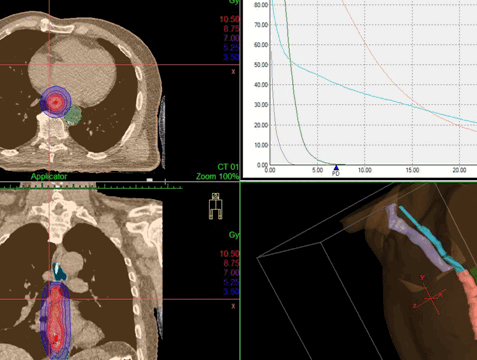

- Контактное (называется «брахитерапия»). Источник излучения эндоскопическим методом размещается как можно ближе к новообразованию. Ионизирующие лучи проходят малое расстояние, поэтому достигают опухоли, но мало затрагивают расположенные рядом ткани. Лечение позволяет уменьшить новообразование и восстановить проходимость.

Дозное распределение, получаемое при дистанционной конформной лучевой терапии и внутрипросветной брахитерапии